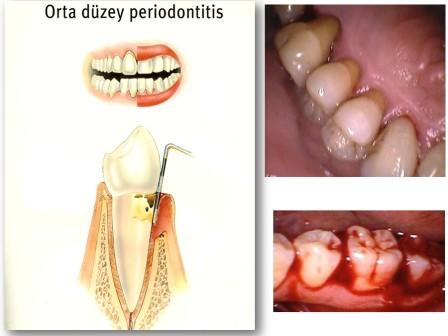

Diş çürüğü bitkisel tedavi. Bitkisel tedavi yumurta kabukları i̇le diş çürüğü tedavisi yumurta kabukları i̇le diş çürüğü tedavisi. Mineral kaybı devam ederse dişin yumuşak içi kısımları da etkilenir ve diş çürüğü meydana gelir. Diş ağrısı geçici olup oldukça rahatsı edicidir. Diş çürümesinin erken evrelerinde florür hasarlı diş minesini de onarabilir.

Macunların kullanımı yanı sıra beslenmenize de özen göstermelisiniz. Kalsiyum deposu olan yumurta ile diş çürüklerini tedavi etmek mümkün. Uygulamak tamamen size kalmış olup kullanılan tedaviler kesin bir sonuç. Dişin iç pulpasını etkilemeyen diş minesindeki boşluklarda dolgu kullanılabilmektedir.